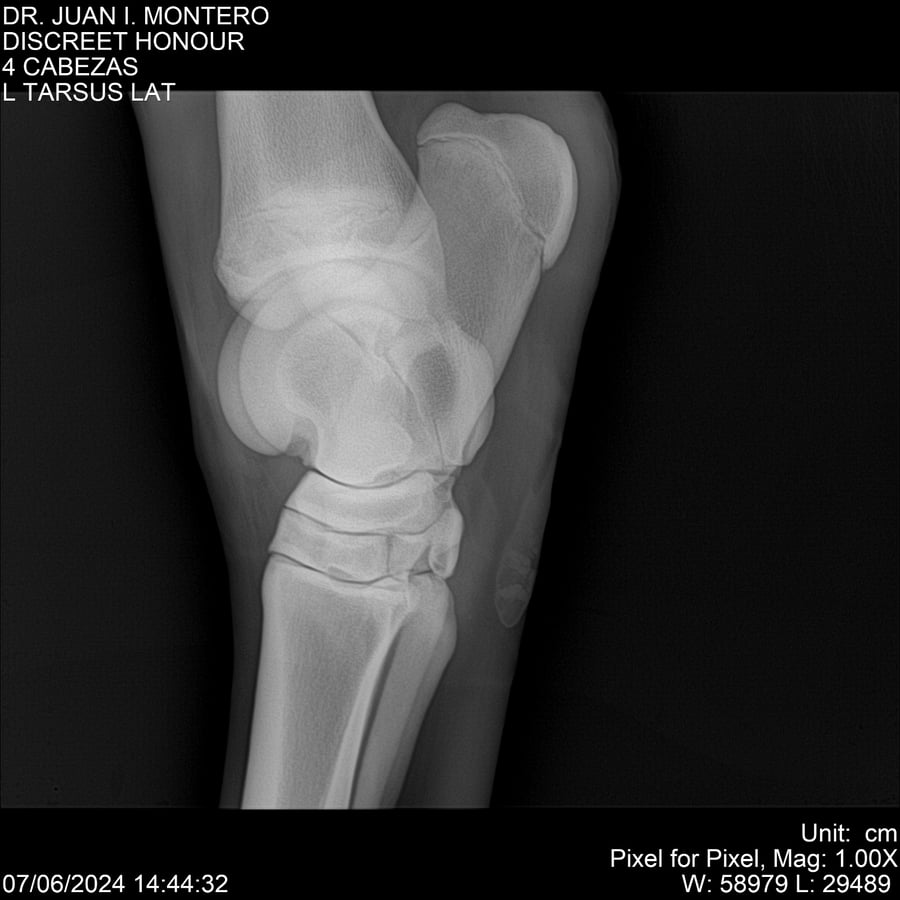

LOTE 6, DISCREET HONOUR 🔥 🔥 🔥 Lote Anterior Volver al remate Lote Siguiente Ficha Contacto Montevideo - Ficha del Lote Identificador: #281093 Categoría: Yeguarizos Montevideo - 82 Visualizaciones ClicData Contacto Empresa: Abelenda N. R., Walter Hugo Nombre*: Teléfono* : E-mail* : Mensaje Enviar Registrese gratis Este contenido Exclusivo está disponible sólo para usuarios registrados Ingresar